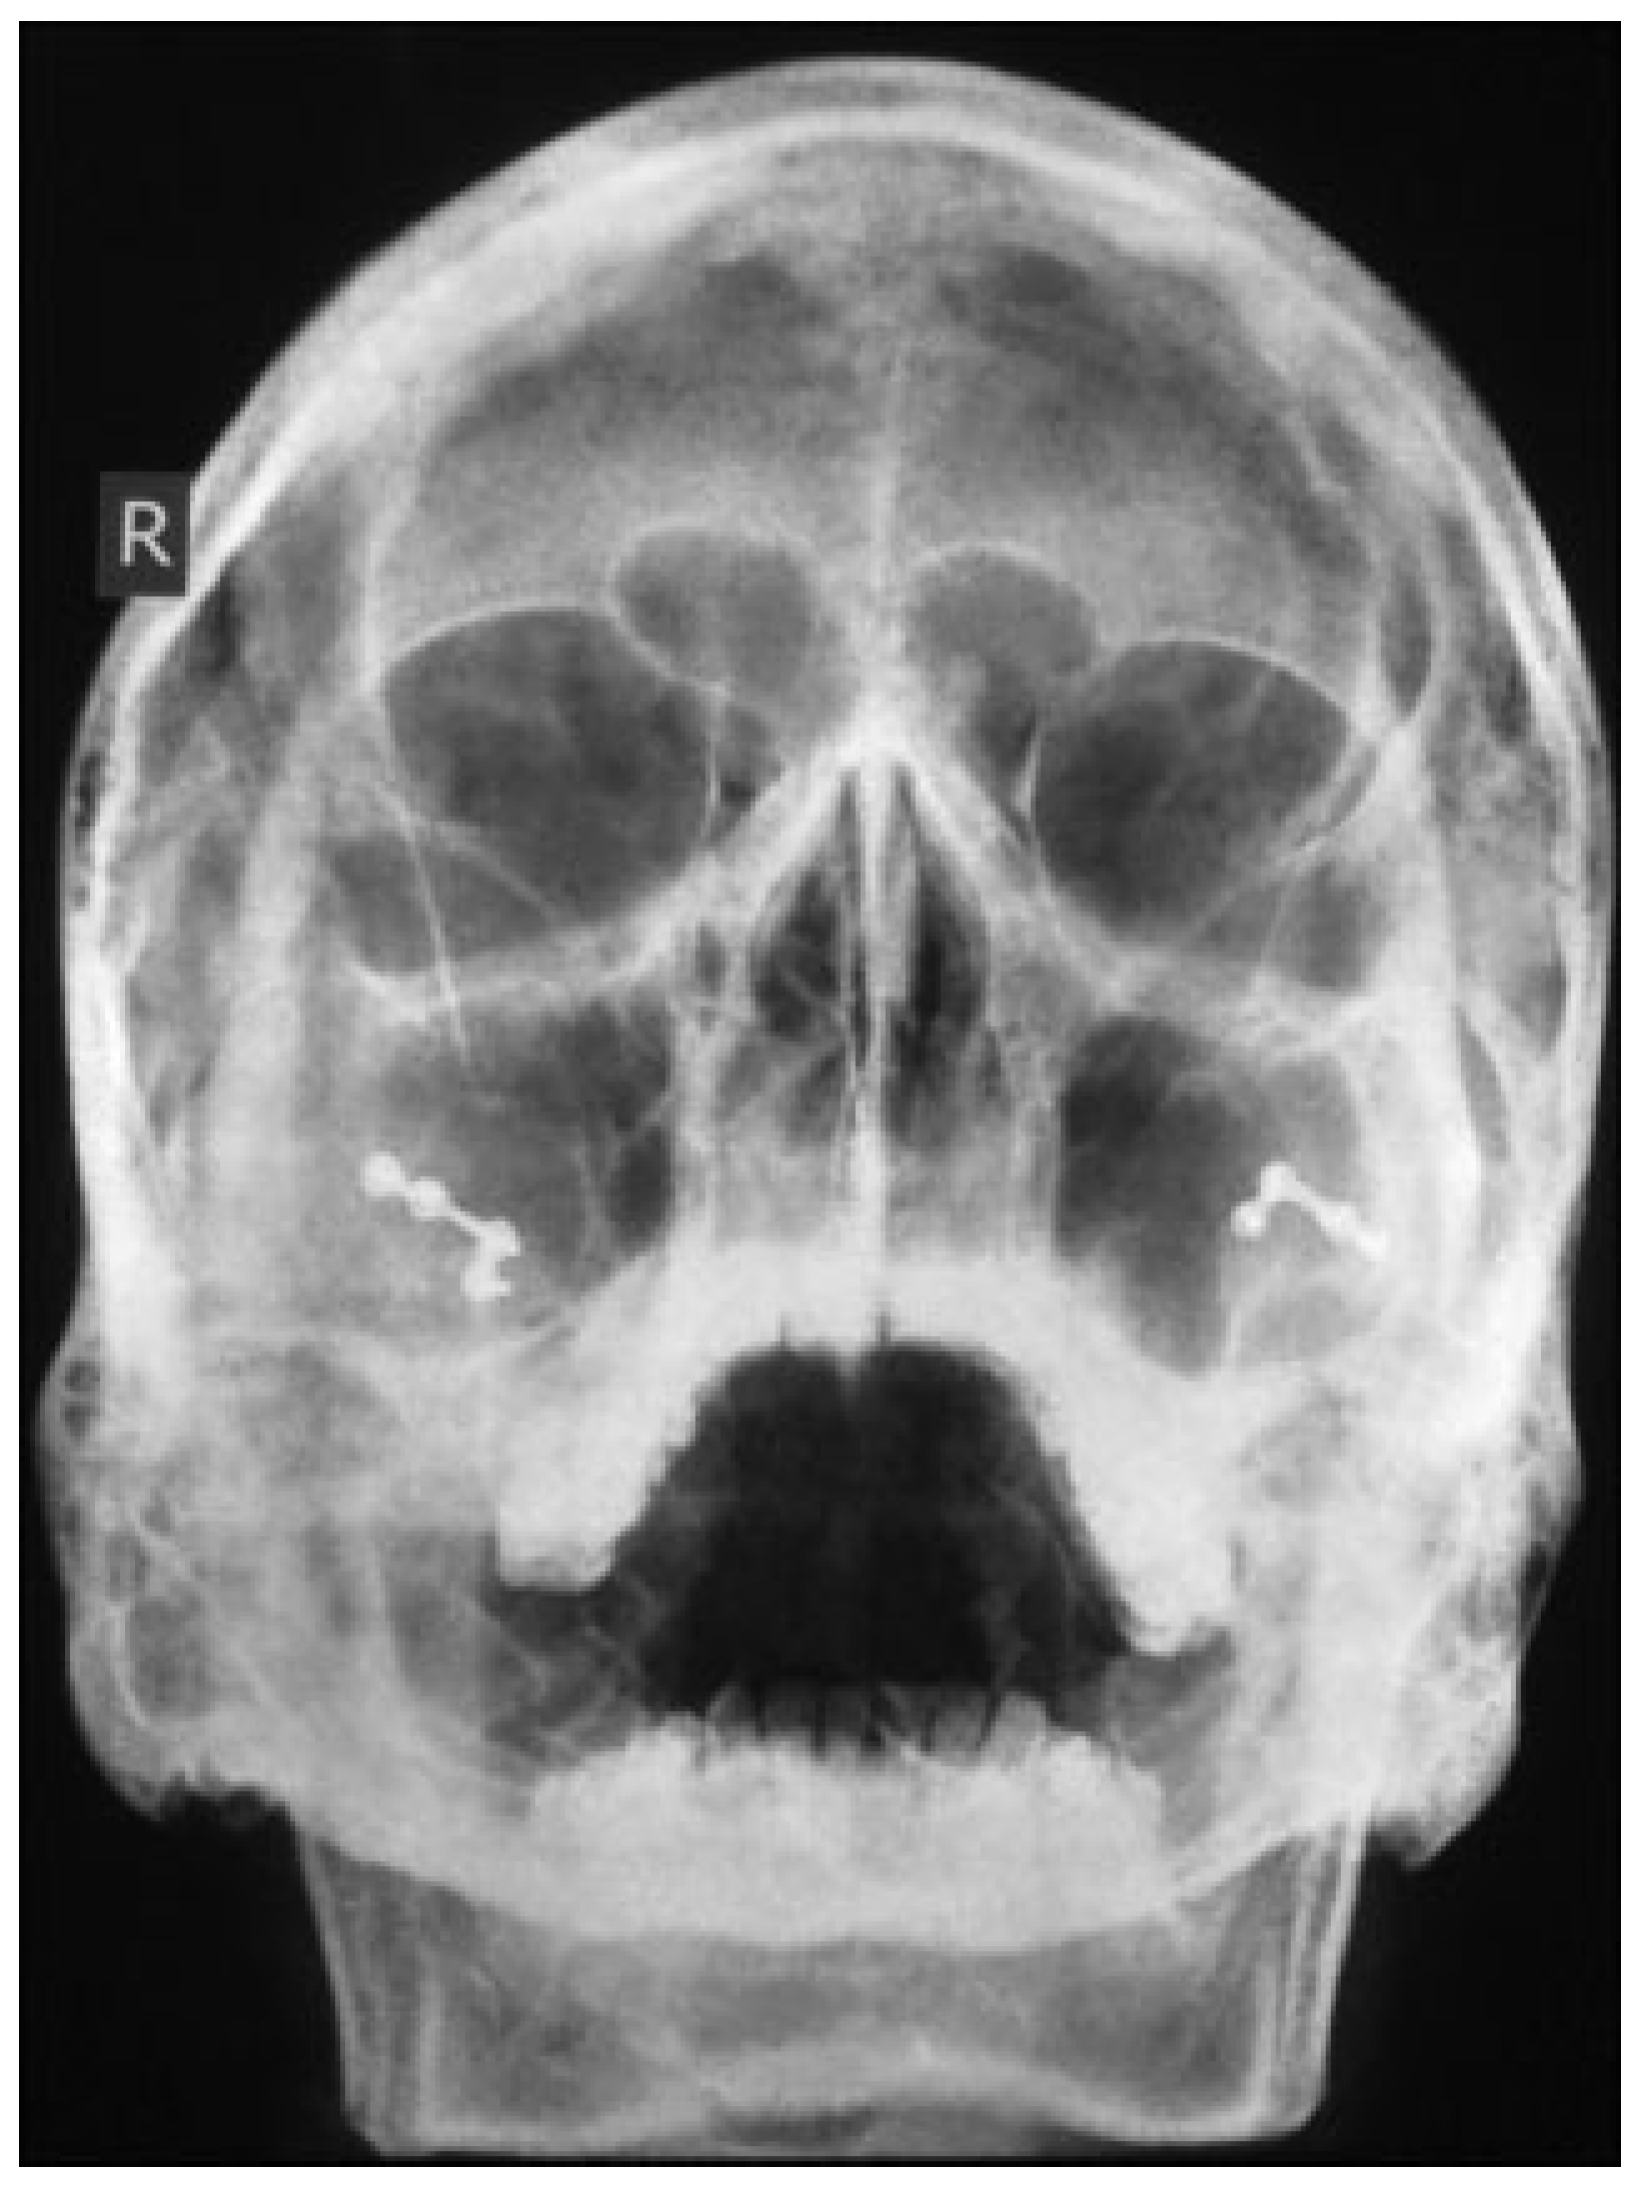

A 35-year-old male patient presented to Accident and Emergency Department with facial injuries associated with RTA. As per the patient, he collided with another motorbike and was not wearing a helmet at the time of accident. On examination, he had bruises on bilateral zygomatic areas and a 2-cm laceration on the right supratarsal fold close to zygomaticofrontal suture. The right and left zygoma were tender on palpation and associated with depression of zygomatic arch areas. Infraorbital paresthesia was present on the right side. Trismus was moderate, and a detailed clinical and computed tomography examination showed displaced bilateral isolated zygomatic complex (Figure 1 and Figure 2) and arch fractures (Figure 3) without any other associated facial bone fractures. He underwent open reduction and internal fixation of both zygomatic complexes including the closed reduction of the arch by Gillies approaches and fixation via an intraoral approach at the Lefort level I (Figure 4). The postoperative recovery was uneventful with good mouth opening and with no cosmetic deficit.

Figure 4. Paranasal sinus view showing open reduction and internal fixation.